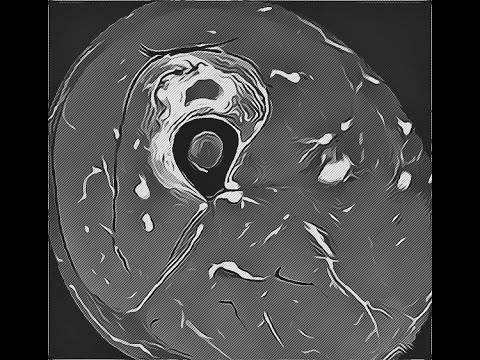

A reactive process characterized by a well-circumscribed proliferation of fibroblasts, cartilage, and bone within the muscle.

A synonym for myositis ossificans is heterotopic ossification. There are several clinical subtypes of myositis ossifican